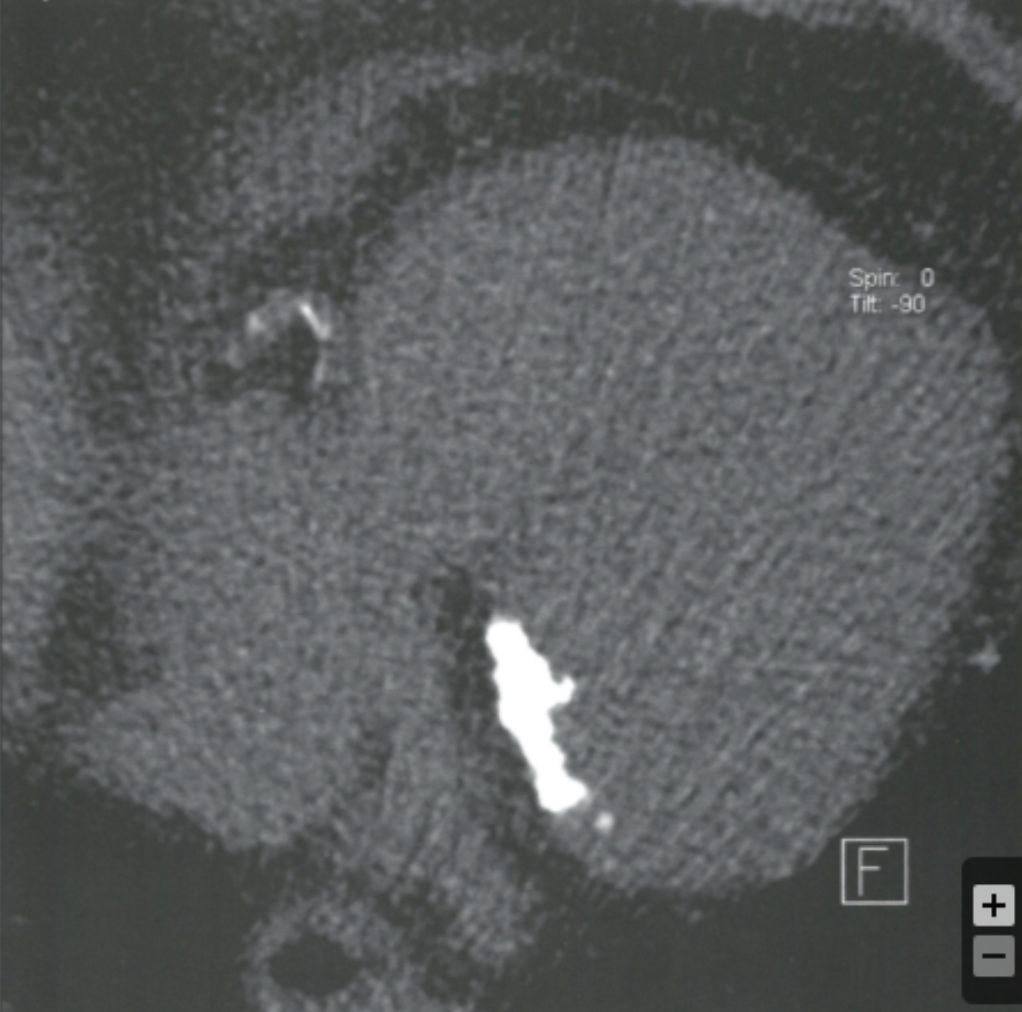

Describe the findings:

Coronary Sinus

Describe the findings and most likely finding on coronary angiorgram

Occlusion in LCFx territory